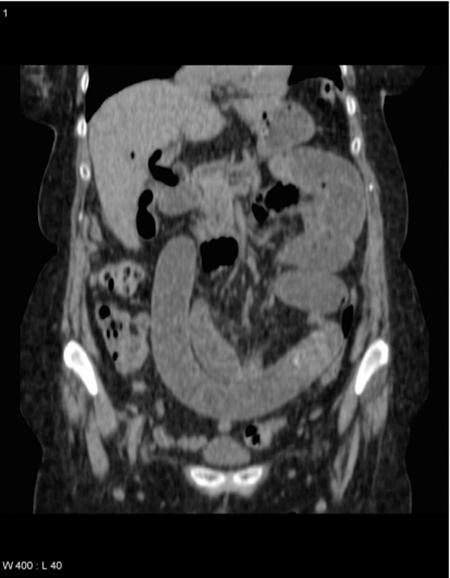

Gallstone ileus is a well-recognized clinical entity. It usually affects elderly female patients, and very often diagnosis can be delayed resulting in high morbidity and mortality. An abdominal x-ray and computed tomographic (CT) scan of the abdomen may show classical radiological features of small bowel obstruction, pneumobilia, and an ectopic gallstone. Laparotomy and enterlithotomy with or without definite biliary surgery is an established treatment. Since 1992, many cases of laparoscopic-assisted enterolithotomy have been reported. Only a few cases of a totally laparoscopic approach have been documented. We present the case of a 75-year-old lady who presented with features of intestinal obstruction. A plain x-ray of the abdomen and a CT scan confirmed the classical features of gallstone ileus. A totally laparoscopic enterolithotomy was performed using 6 ports. A 6-cm gallstone was retrieved through a longitudinal enterotomy. The transverse closure of the enterotomy was performed with intracorporeal suturing, resulting in an uneventful postoperative recovery. We suggest that a CT scan helps in the early diagnosis of the cause of intestinal obstruction, and totally laparoscopic enterolithomy with intracorporeal enterotomy repair is a valid, safe option.

胆石性肠梗阻是一种广为人知的临床病症。它通常影响老年女性患者,而且诊断往往会延迟,导致高发病率和死亡率。腹部X线检查和腹部计算机断层扫描(CT)可能显示小肠梗阻、胆系积气和异位胆结石的典型影像学特征。剖腹手术和肠石切除术,无论是否进行确定性胆道手术,都是既定的治疗方法。自1992年以来,已有许多腹腔镜辅助肠石切除术的病例报道。仅有少数完全腹腔镜手术的病例有文献记载。我们报告一例75岁女性患者,她表现出肠梗阻的症状。腹部平片和CT扫描证实了胆石性肠梗阻的典型特征。使用6个端口进行了完全腹腔镜肠石切除术。通过纵向肠切开取出了一枚6厘米的胆结石。肠切开处采用体内缝合进行横向闭合,术后恢复顺利。我们认为CT扫描有助于早期诊断肠梗阻的病因,完全腹腔镜肠石切除术及体内肠切开修复是一种有效、安全的选择。